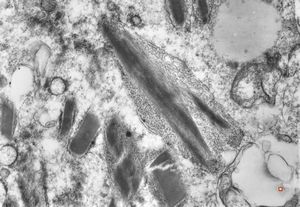

bone marrow - crystalloid inclusions Charcot-Leyden crystals formation

bone marrow - crystalloid inclusions Charcot-Leyden crystals formation v.s.